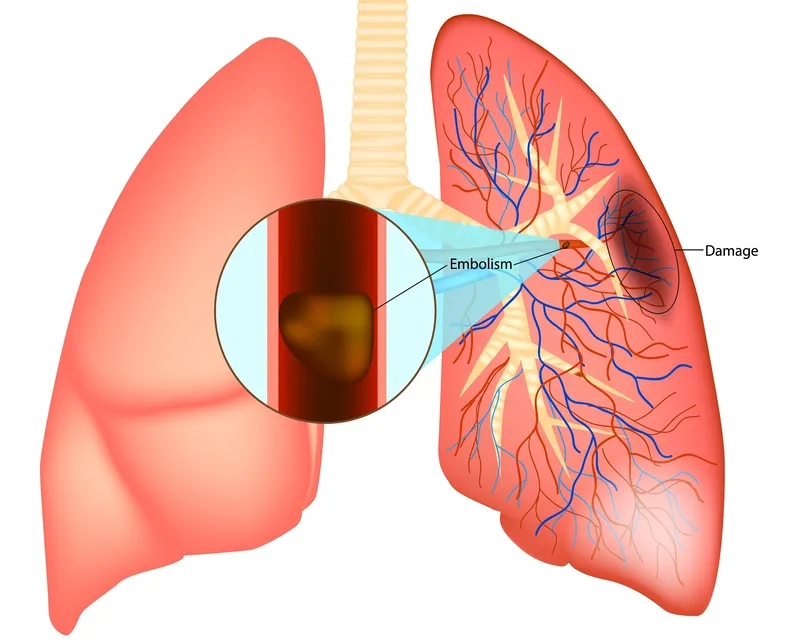

• One of the main causes of pulmonary embolism is a blood clot from a deep vein thrombosis (DVT) in the leg that breaks free.

• This dislodged clot travels through the bloodstream to the lungs, where it becomes stuck in an artery, blocking vital blood flow to lung tissue.

Image of a Pulmonary Embolism in the Lungs

An illustration of what is a pulmonary embolism in the lungs